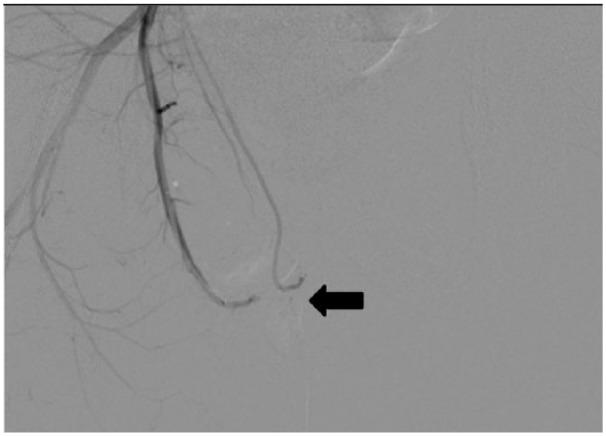

Priapism is a persistent erection of the penis not associated with sexual stimulation. High-flow priapism is caused by unregulated arterial inflow, usually preceded by perineal or penile blunt trauma and formation of an arterial-lacunar fistula. We present a case of high-flow priapism in a 13-year-old patient managed with polyvinyl alcohol particles.

After obtaining informed consent of the parents of the minor, diagnosis was made with penile Color Doppler Ultrasound and confirmed with flush angiography. Selective arterial embolization was performed with the use of polyvinyl alcohol particles.

Complete detumescence was achieved without compromising the patient's erectile function.